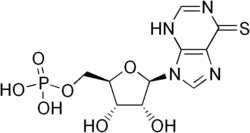

Thioinosinic acid

| IUPAC name

[(2R,3S,4R,5R)-3,4-Dihydroxy-5-(6-sulfanylidene-3H-purin-9-yl)oxolan-2-yl]methyl dihydrogen phosphate

| Other names

Thioinosine monophosphate (TIMP)

| C10H13N4O7PS | |

| Molar mass | 364.27 g/mol |

Thioinosinic acid (or thioinosine monophosphate, TIMP) is an intermediate metabolite of azathioprine, an immunosuppressive drug.[1][2]